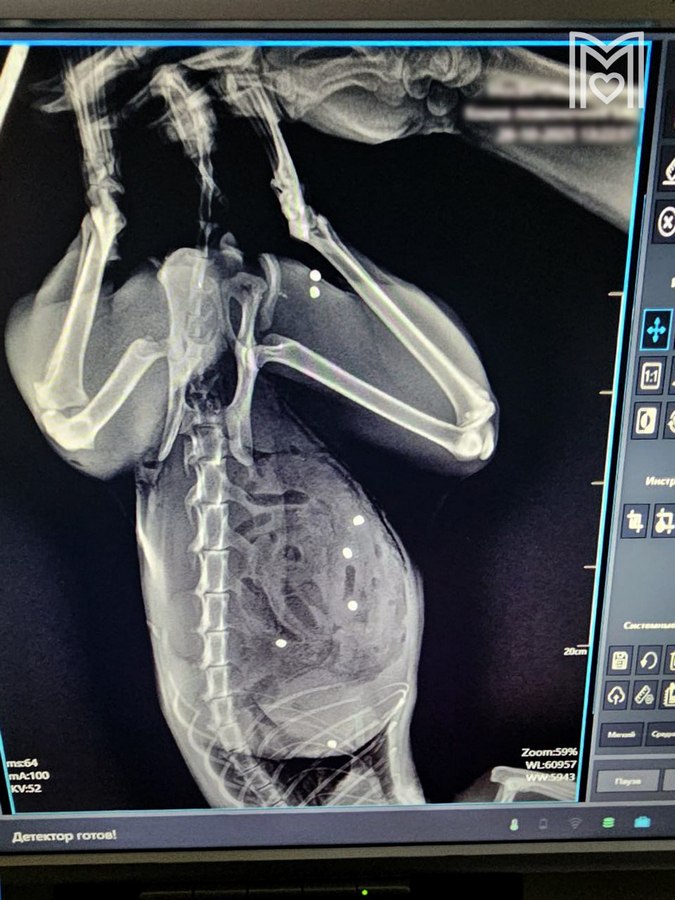

В Зеленограде успешно прооперировали кота, у которого был в 24 местах пробит кишечник.

Кота оперировал хирург Евгений Цыбин. Выяснилось, что у Тимофея в 24 местах пробит кишечник и в двух —селезенка, также пули попали в грудную клетку и мышцы бедра. Операция продолжалась больше трех часов. В итоге почти безнадежный пациент был спасен, говорится в сообщении. «Под конец операции и кот, и я выглядели одинаково... Не скрою, горжусь собой на 100%, но еще больше котом! Несмотря нa все усилия живодеров, котик жив!» — рассказал сам хирург Цыбин.